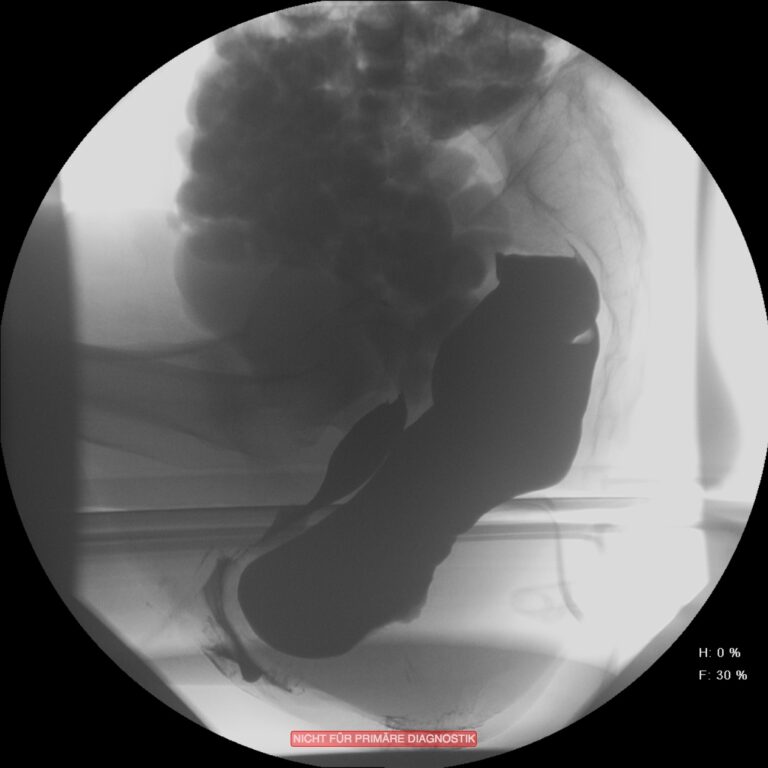

In vielen Fällen ist diese Obstruktion mit einer gleichzeitig bestehenden Inkontinenz kombiniert. Dies erscheint auf den ersten Blick etwas paradox. Durch die andauernde unvollständige Entleerung ist die Rektumampulle aber nie vollständig geleert und der Schließmuskelapparat durch die ständige Überdehnung des Beckenbodens nicht in der Lage, den Stuhlgang immer suffizient zurückzuhalten. Zur Differentialdiagnostik werden Sphinktermanometrie, Endosonografie, Rektoskopie und ein Röntgenverfahren, die Defäkografie angewendet. Diese erlaubt eine Darstellung der funktionellen Abläufe und anatomischen Veränderungen während der Defäkation. Das Ausmaß der Obstruktion und der Inkontinenz wird mit anamenstischen Score-Werten objektiviert.